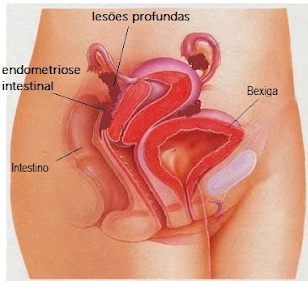

Nós, fisioterapeutas que trabalhamos com terapia manual e osteopatia, entendemos que em muitos casos a origem da dor ciática pode estar relacionada a congestões, tensões e aderências nas vísceras (órgãos internos).

Essas vísceras são envolvidas por tecidos chamados fáscias, que fazem conexão com músculos, nervos e articulações. Quando essas fáscias perdem mobilidade, podem gerar tensão à distância.

Quando a dor ciática aparece especificamente na perna direita, é comum observar a influência de estruturas como:

• Intestino

Disfunções nessas áreas podem aumentar a tensão mecânica no corpo e irritar o trajeto do nervo ciático, resultando em dor, formigamento ou sensação de peso na perna.e nessas regiões podem gerar sobrecarga e irritação do nervo ciático.